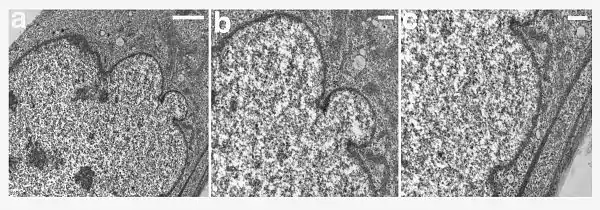

| A young girl with progeria (left). A healthy cell nucleus (right, top) and a progeric cell nucleus (right, bottom). | |

HPGS is caused by mutations that weaken the structure of the cell nucleus, making normal cell division difficult. The histone mark H4K20me3 is involved and caused by de novo mutations that occurs in a gene that encodes lamin A. Lamin A is made but isn't processed properly. This poor processing creates an abnormal nuclear morphology and disorganized heterochromatin. Patients also don't have appropriate DNA repair, and they also have increased genomic instability.[10]

In HGPS, the recognition site that the enzyme requires for cleavage of prelamin A to lamin A is mutated. Lamin A cannot be produced, and prelamin A builds up on the nuclear membrane, causing a characteristic nuclear blebbing.[26] This results in the symptoms of progeria, although the relationship between the misshapen nucleus and the symptoms is not known.

A study that compared HGPS patient cells with the skin cells from young and elderly normal human subjects found similar defects in the HGPS and elderly cells, including down-regulation of certain nuclear proteins, increased DNA damage, and demethylation of histone, leading to reduced heterochromatin.[27] Nematodes over their lifespan show progressive lamin changes comparable to HGPS in all cells but neurons and gametes.[28] These studies suggest that lamin A defects are associated with normal aging.[27][29]